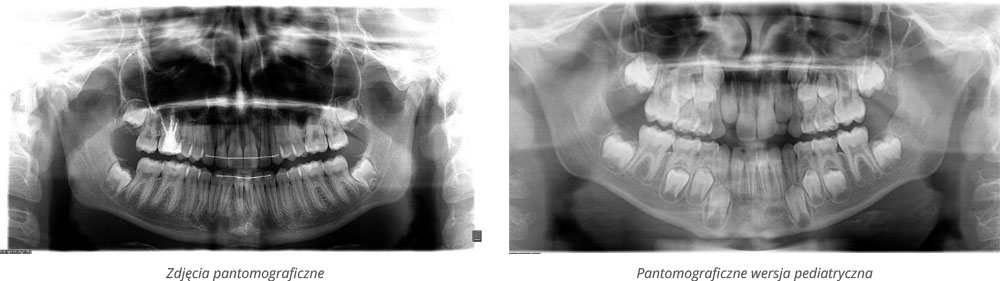

W styczniu wyposażyliśmy naszą pracownię w nowy tomograf komputerowy Orthopantomograph 3D Pro firmy Kavo. Jest on następcą wcześniej stosowanego przez nas aparatu Orthopantomograph OP 200 fińskiej firmy Instrumentarium. Warto wspomnieć, że jako pierwszy gabinet ortodontyczny w województwie opolskim stworzyliśmy w 1997 roku własną pracownię rtg, dla wygody naszej i oczywiście naszych pacjentów. Od wielu już lat, analogowy jeszcze wówczas aparat do zdjęć pantomograficznych z przystawką do cefalomoetrii włoskiej produkcji, jest jednym z eksponatów największego na świecie Muzeum Lamp Rentgenowskich znajdującego się na Politechnice Opolskiej.

Jest to uniwersalny tomograf z innowacyjna technologią niskiej dawki Low Dose Technology, automatyczną kontrolą dawki. Jest to szczególnie istotne przy wykonywaniu zdjęć kontrolnych u dzieci.

Aparat ten pozwala na uzyskanie precyzyjnych obrazów 2D dzięki funkcji multilayer i technologii wiązki RTG w kształcie litery V. Badanie może być wykonane w 4 rozdzielczościach obrazu w trybie 3D. Posiada funkcję redukcji artefaktów z metalowych elementów. Ma również 5 wielkości pól obrazowania.

Dla wszystkich pięciu pól obrazowania można wybrać jeden z trzech trybów rozdzielczości. Dla skanu 5/5 dodatkowo dostępny jest też tryb Endo.

Ilustracja obu łuków zębowych i części zatok szczękowych: